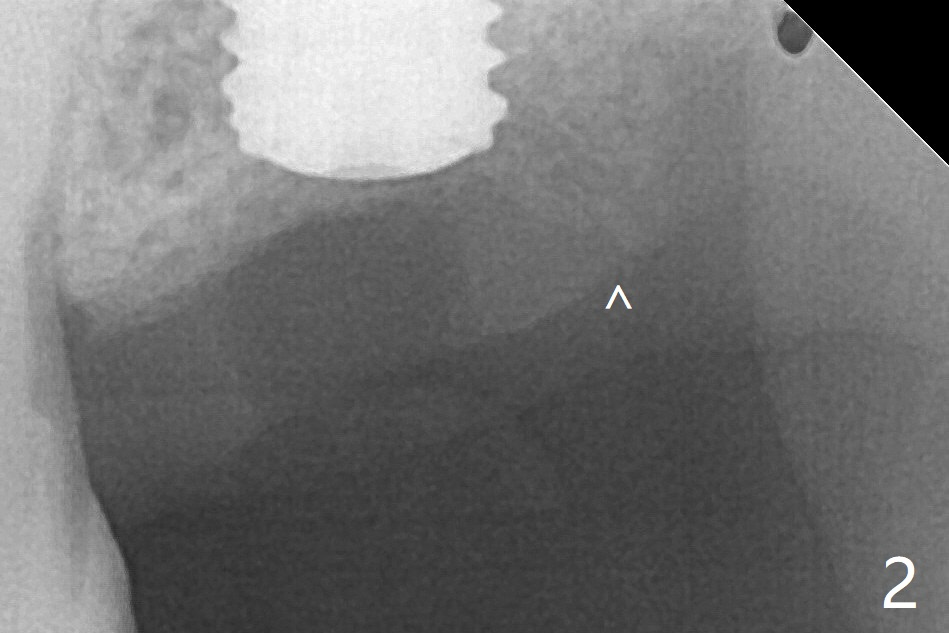

Following shorter drill sequence at #15, sinus round drills (18 and 19 mm long) are used to perforate the sinus floor without membrane tear. With autogenous bone for sinus lift (Fig.1 S), a 5x7.3 mm implant is placed with high torque in spite of using 5 mm cortical drill with 3 O-rings. Clinically there appears no hard tissue distal, although the bone density (graft bone in the 3rd molar socket) is low shown in bitewing (Fig.2 ^). Allograft is applied around the distal coronal portion of the implant before placement of Osteogen Plug and 4-0 PGA suture (Fig.3 *). Profile drill is required during uncover. With sensor I, there is less distortion and angulation (Fig.4, as compared to Fig.1 (sensor II)). A 5.5 mm profile drill is used prior to healing abutment placement.